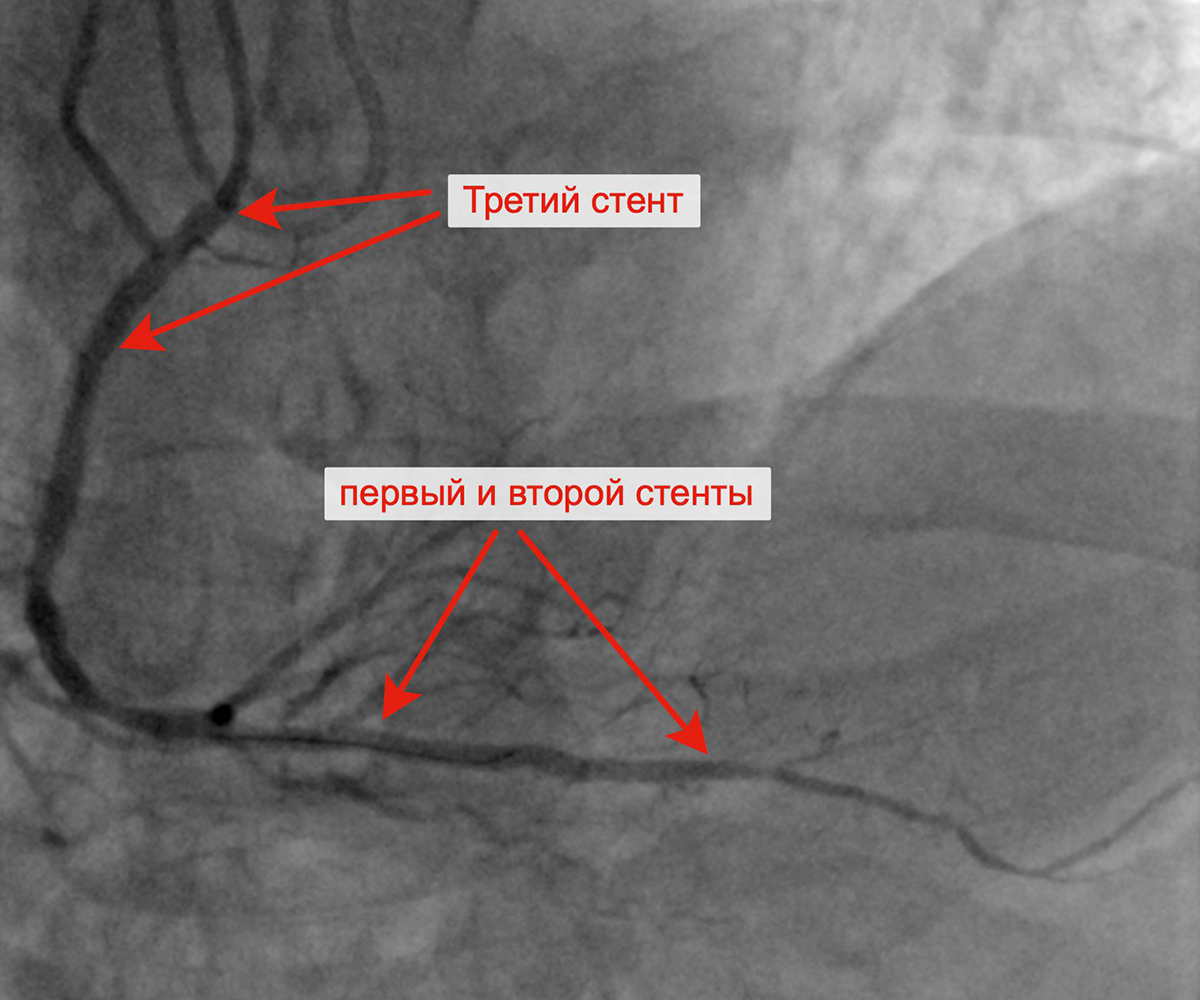

Чрескожное коронарное вмешательство (ЧКВ) на хронической окклюзии ПКА выполнялось билатеральным лучевым доступом: через левую лучевую артерию диагностическим катетером параллельно выполнялись съемки ЛКА, что позволило визуализировать через межсистемные коллатерали дистальное русло постокклюзированной ЗМЖА и контролировать процесс реканализации хронической окклюзии и проведение коронарного проводника в дистальное русло ЗМЖА. Успешно была выполнена реканализация ЗМЖА, баллонная ангиопластика и стентирование правой коронарной артерии (3 стента с лекарственным покрытием). При контрольной ангиографии: стенты и ПКА проходимы, позиционирование стентов адекватное, диссекции или остаточного стеноза в стентированных сегментах ПКА нет, кровоток TIMI 3 по ПКА и всем ветвям. Пациент был на следующий день выписан из клиники.

Позиционирование первого стента в ПКА после предилатации Позиционирование второго стента в ПКА

с билатеральным контрастированием

Имплантация третьего стента в ПКА от устья артерии Финальный результат реканализации, баллонной

ангиопластики и стентирования ПКА тремя стентами